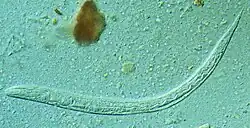

Strongyloides stercoralis

Species: Strongyloides stercoralis

English: Threadworm